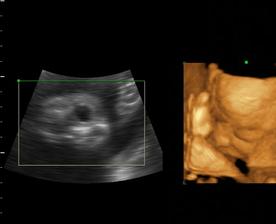

Naša maličká Emka alebo Silvinka...🙂

Od 19. júna 2008, teda od 21. týždňa vieme, že sa nám na 99% narodí dievčatko...na mene neodznela ešte úplná zhoda, preto Ema alebo Silvia...no ja dúfam, že sa mi podarí presadiť Emu, aj keď Silvia je tiež krásne meno...🙂...